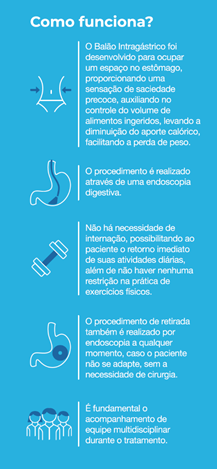

Como funciona o balão intragástrico?

O balão intragástrico ocupa um espaço dentro do estômago e o paciente fica com sensação de plenitude e saciedade precoce. Em outras palavras, sobra menos espaço para os alimentos, diminuindo o volume ingerido nas refeições.

Durante o período de tratamento, é essencial um acompanhamento multidisciplinar que permita reeducação alimentar e mudança do estilo de vida, garantindo assim o sucesso e a manutenção da perda de peso após a retirada do balão.

Quais as indicações para o tratamento com balão intragástrico?

O tratamento é indicado para pacientes com obesidade (IMC acima de 30), com ou sem doenças relacionadas ao excesso de peso, e que já tenham tentado diversos tipos de tratamentos clínicos para emagrecer, sem sucesso.

O tratamento também é indicado para pessoas obesas que irão se submeter a algum tipo de cirurgia, pois o balão auxilia na perda de peso e, consequentemente, reduz de maneira considerável o risco cirúrgico.

O tempo de duração desse tratamento é de seis a 12 meses, dependendo da prótese utilizada. Após esse período, ele deve ser retirado.

Após a retirada do balão, é indicado que o tratamento tenha continuidade por pelo menos mais um ano com o acompanhamento de endocrinologista e nutricionista.